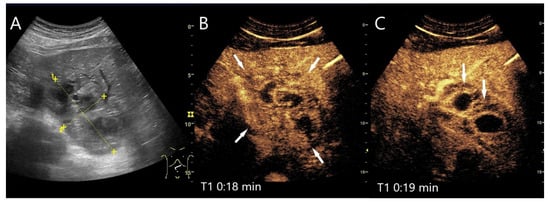

Figure 7.

ß-catenin-mutated HCA. Female patient. Incidental findings of a 19 × 17 mm hyperechoic FLL on B-mode US (arrow) (A). CEUS shows arterial hyperenhancement after 23 s (B). The center is less hyperenhanced. After 2:14 min, the lesion shows a slight washout (arrow) (C). The US-guided biopsy (D) revealed the diagnosis of a ß-catenin mutated HCA.